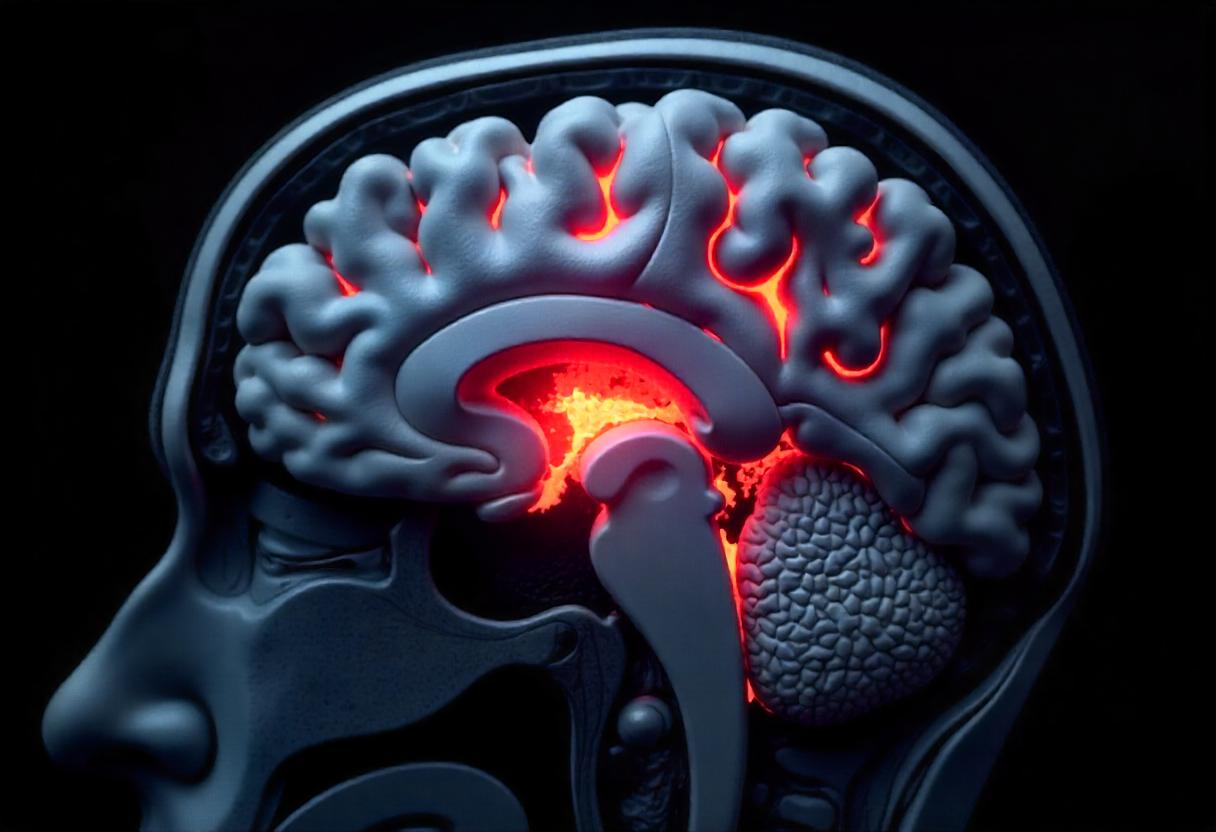

Understanding Glioblastoma – The Most Aggressive Brain Tumor

At Askdoctor.ai, we understand that a diagnosis of glioblastoma can be overwhelming, not just for patients but for their families…